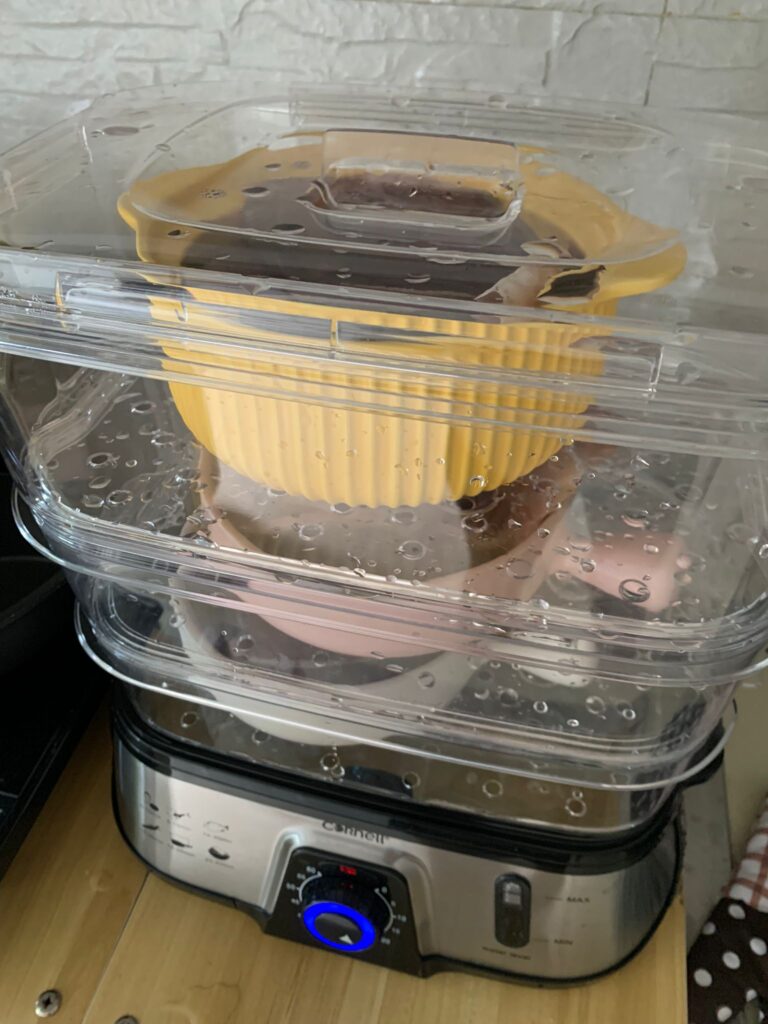

Morning: got helper in to cut nails, steam bath and clean ears. She can handle him alone. Given Subcut bupre n put on f patch for him.

Morning: got 2 helpers in to clean up and for him: cut nails, clean ears and steam brush fur. His f patch if off, given Subcut and bupre jab